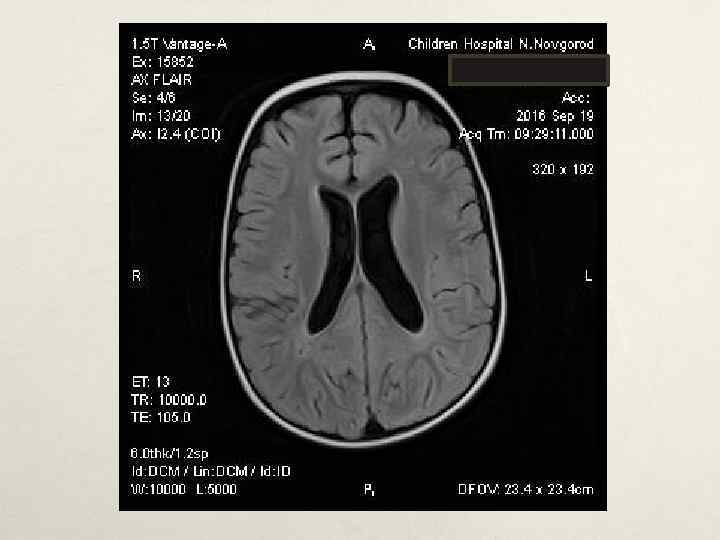

Клинический случай № 1 • В нейрохирургическом отделении: • МРТ головного мозга с КУ от 19. 05. 2016 – картина кистозно-солидного образования мозжечка, внутренняя окклюзионная гидроцефалия • Проведена операция – трепанация задней черепной ямки, удаление опухоли левой гемисферы мозжечка. Согласно гистологическому заключению и пересмотра препаратов в НИИ им. Бурденко – пилоидная астроцитома Grade I. МРТ головного мозга с КУ в динамике – остаточная опухоль 1. 7*1. 8*2. 3 см в левой гемисфере мозжечка. • • • В лечении: диакарб, аспаркам, дексазон, цефтриаксон, этамзилат, глюкозо-солевые растворы, СЗП, Er-масса, альбумин, симптоматическое. • В неврологическом статусе симптоматики, атаксии. регресс общемозговой